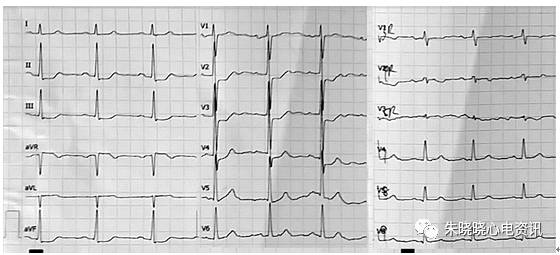

图3 患者男性,56岁。

间断性胸痛4天,加重并呈持续性胸痛2小时。既往有高血压病史10年。先登场提示V2-4导联和II、III、aVF导联ST段压低0.1mV,V8-9轻度ST段抬高(0.02mV)。入院后肌钙蛋白(cTnI)肌红蛋白均明显升高。冠脉造影显示左回旋支中段完全闭塞(箭头指示),随后开通闭塞病变并植入支架。